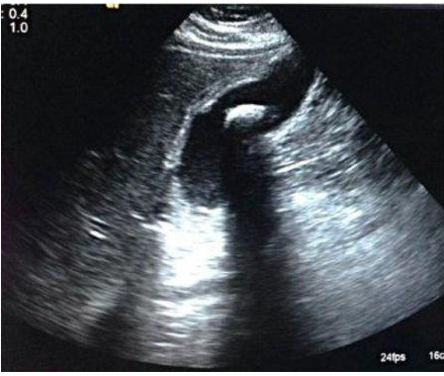

Shadowing artifact occurs secondary to the reflective and attentive properties of the imaged structure. As seen in this example, the gall bladder stone is highly attenuating and reflectiv3e leading to complete abscence of sound waves behind the stone.